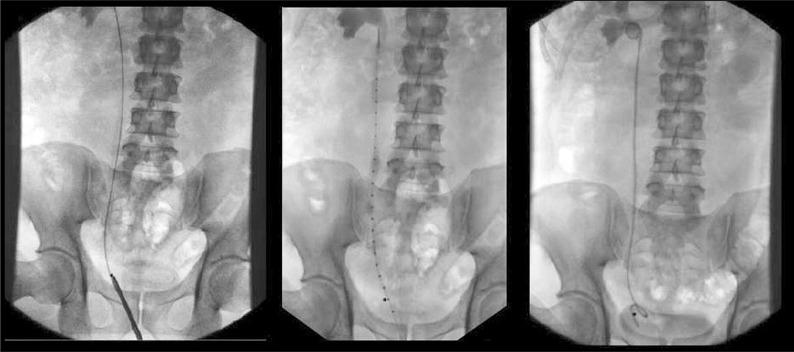

301 urologists (15.1%) responded to our survey. Following ureteroscopy, 84.5% of respondents would stent at least 50% of the time. Following uncomplicated ureteroscopy, most respondents (52.0%) would leave a stent for 2-7 days. Patient height was most commonly ranked first as the method of choice in determining stent length (47.0%), followed by estimation based on experience only (20.6%) and intra-operative direct measurement of ureteric length (19.1%). Most respondents utilized multiple methods in determination of optimal stent length. Most respondents (66.5%) were interested in a simple intra-operative technique utilizing a special ureteral catheter that would help choose the most appropriate stent length.

Post-ureteroscopy stent insertion is common and patient height is the most common method of choice used in determining optimal stent length. Most respondents were interested in using a simple, novel ureteral catheter device that would allow them to more accurately select optimal stent length.

301名泌尿外科医生(15.1%)回复了我们的调查。输尿管镜检查后,84.5%的受访者至少50%的时间会置入支架。在无并发症的输尿管镜检查后,大多数受访者(52.0%)会留置支架2 - 7天。患者身高最常被列为确定支架长度的首选方法(47.0%),其次是仅基于经验的估计(20.6%)和术中直接测量输尿管长度(19.1%)。大多数受访者在确定最佳支架长度时采用多种方法。大多数受访者(66.5%)对一种利用特殊输尿管导管的简单术中技术感兴趣,该技术有助于选择最合适的支架长度。

输尿管镜检查后置入支架很常见,患者身高是确定最佳支架长度时最常用的首选方法。大多数受访者对使用一种简单的新型输尿管导管装置感兴趣,该装置能使他们更准确地选择最佳支架长度。